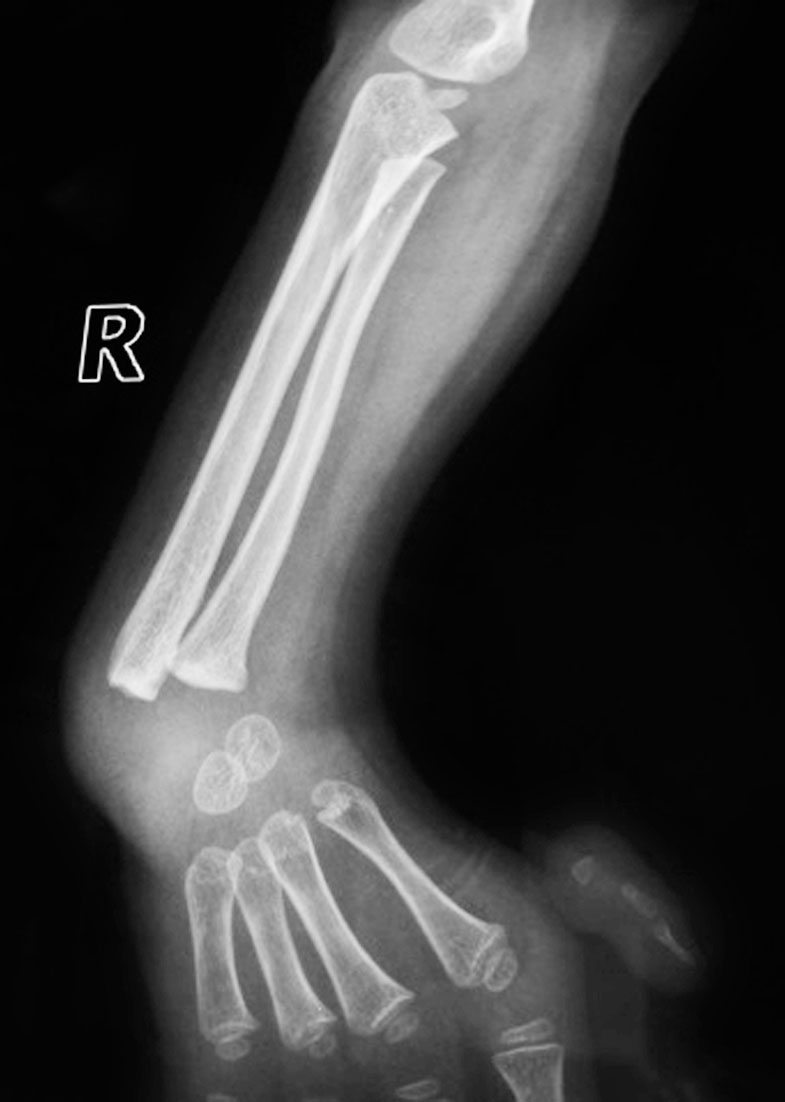

(1)近端桡、尺骨骨性融合(图1-2-22)。

图1-2-22 先天性前臂桡、尺骨近端骨性融合